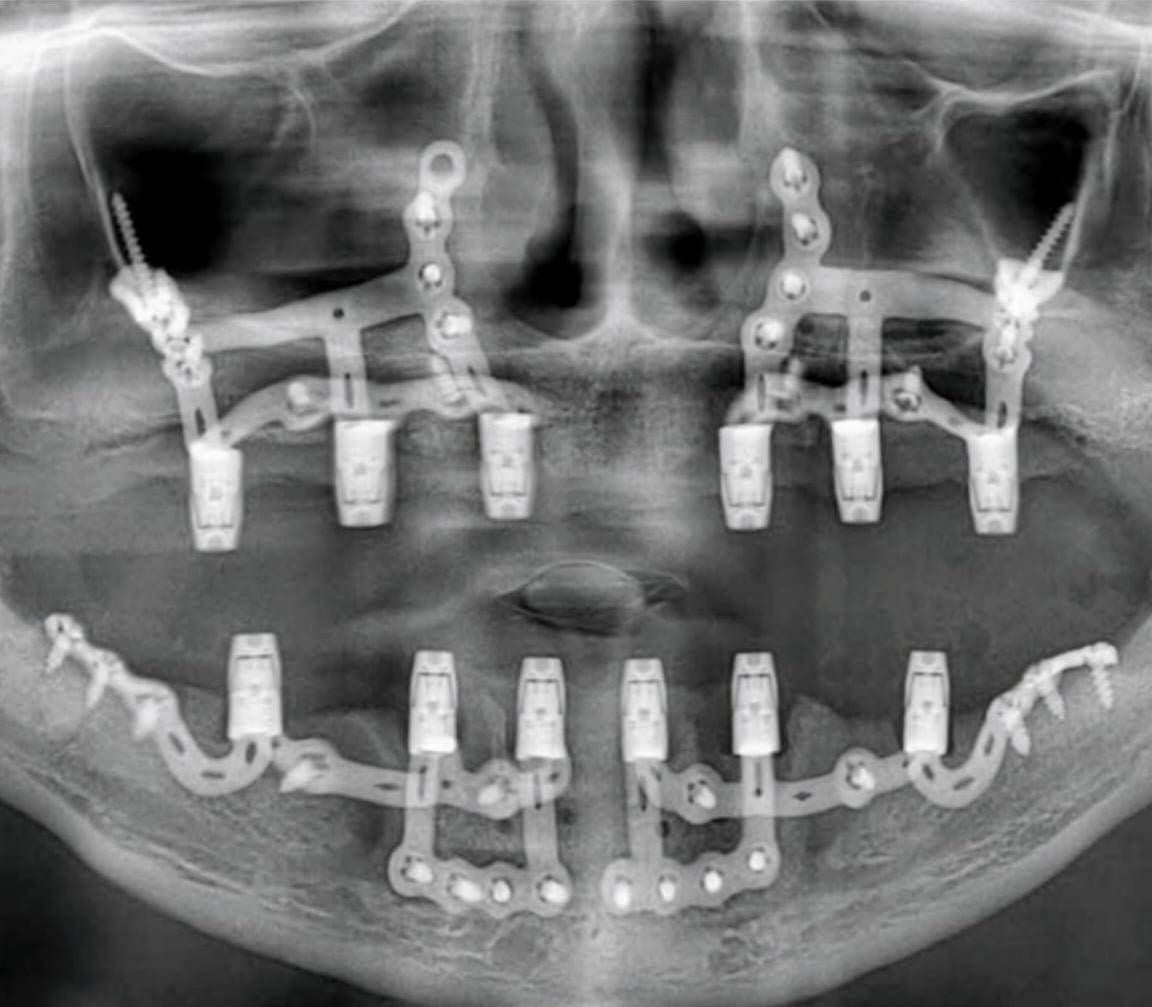

3. Surgical Application

Although the operation can be performed under local anesthesia, general anesthesia is generally more preferred.

The surgeon gains access under the gum (gingiva) and fixes the implant skeleton to the bone surface.

The “abutments,” to which the dental prostheses will be attached, mostly come connected to the implant unit. The surgical procedure is concluded by attaching healing caps to these units.

4. Prosthesis Stage

Shortly after the implant skeleton is fixed, the fixed prosthesis (bridge or full-arch restoration) is attached to the patient.

It is usually possible to have permanent fixed teeth within 2–3 weeks.